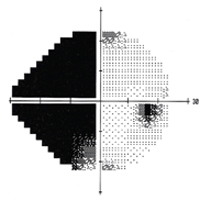

GlaucomaImage

Michael L. Savitt, MD

Assistant Professor and Director, Section of Glaucoma

Image

Specialty glaucoma clinics are held throughout the week so that complex glaucoma patients can be seen with fellowship trained glaucoma specialists. Additionally, glaucoma patients are seen in the general clinic with general ophthalmology attendings throughout the week. One resident reads

automated visual field tests one day per week in a one-on-one session. An excellent experience in surgical glaucoma therapy is provided; approximately four glaucoma surgical procedures are done each week, with residents as the primary surgeon in Eye Center cases. Surgical experience is gathered in standard trabeculectomy, MIGS procedures, antimetabolite assisted procedures, peripheral iridectomies, goniotomy, and placement of seton tubes and valves. Residents are expected to become proficient in all procedures as primary surgeon. In addition, experience is gained in cyclodestruction procedures with either cryotherapy, contact YAG or contact diode laser, selective laser trabeculoplasty, thermal laser trabeculoplasties and laser peripheral iridotomies. Emphasis is placed on modern nerve fiber analysis with the OCT. By the end of the training, residents are able to examine and treat all aspects of glaucoma medically and surgically. The Glaucoma Section faculty who participate in the resident continuity clinic include Section Director Michael L. Savitt, MD, MD, Madhu S.R. Gorla, MD, Nina A Goyal, MD, Anjali S. Hawkins, MD, PhD, Brian Herst, MD, Brian J. Jacobs, MD, Hreem Patel, MD, and Rebecca Sarran, MD. -